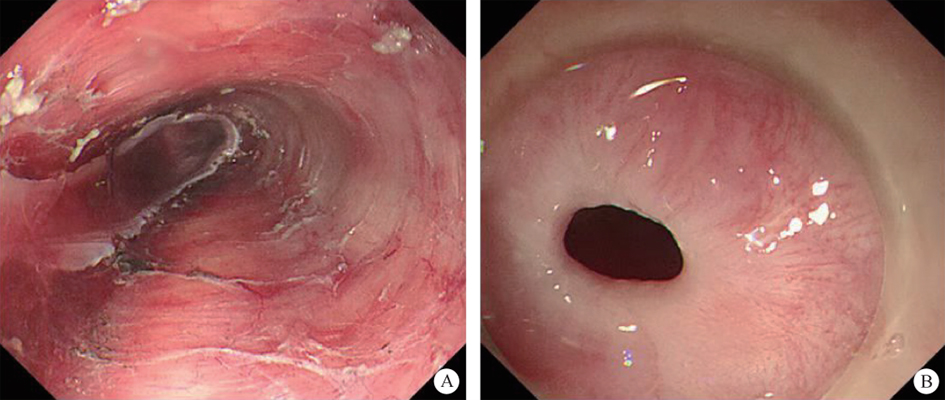

1. Peroral endoscopic myotomy (POEM). POEM has been widely used in the clinical treatment of achalasia; recently, applications in other parts of the human body have also been gradually emerging. In 2020, a study was conducted on a group of eight patients esophageal diverticulum and esophageal diverticulum treated by using POEM, also known as peroral diverticulum myotomy (D-POEM). D-POEM establishes a tunnel under the esophageal mucosa and incises the ridge between the diverticulum in the tunnel to make the diverticulum disappear. Postoperative follow-up of all patients, their preoperative symptoms were improved, and no adverse events were reported. Studies have shown that D-POEM has a certain effect on esophageal diverticulum, and that it is not affected by the position of the diverticulum and the length of the ridge between them, making it a safe and effective operation.